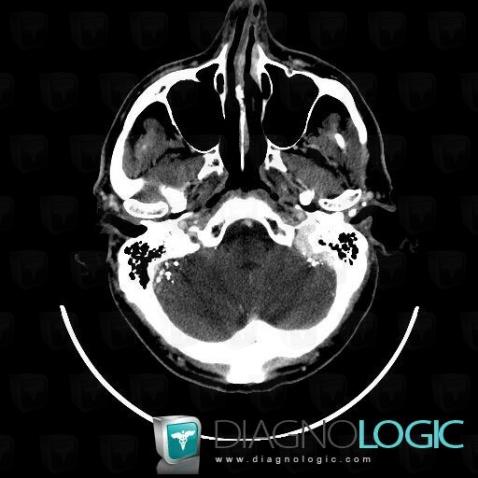

Lipiodol injection, Infratentorial peri cerebral spaces, CT

Here is the specific information in the key image above:

- Diagnosis Lipiodol injection, Location(s) Infratentorial peri cerebral spaces, with gamuts Basilar cisterns anomaly, Infratentorial extra axial lesion